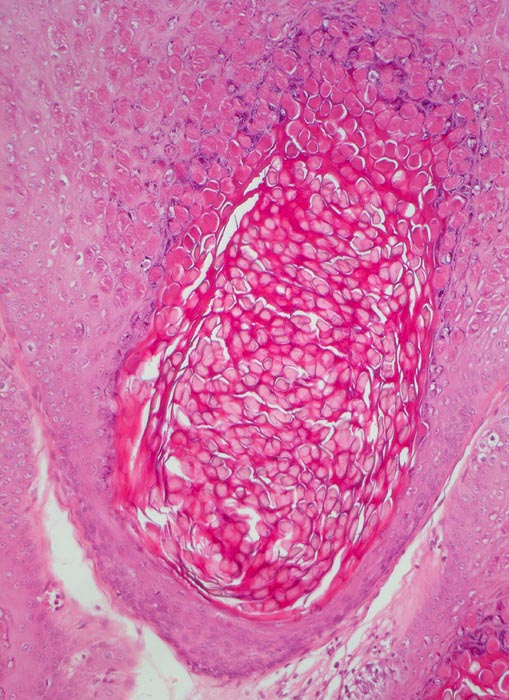

Dellwarzen imponieren als schmerzlose oder juckende fleischfarbene Knötchen mit einem zentralen Nabel (Delle). Sie treten einzeln oder multipel auf (meist nicht mehr als 20). Der Durchmesser beträgt meist 2-6mm, selten bis zu 3cm. Eine bakterielle Superinfektion der Läsionen mit Pustelbildung und Erythem ist möglich. Die Epidermis ist akanthotisch und kann bis zu 6 mal dicker sein als normal. Die Basalzellen sind etwas vergrössert und hochprismatischer. Das Molluscum Körperchen ist das Ergebnis einer viral induzierten Zytoplasmareaktion. Die multiplen intrazytoplasmatischen Einschlüsse enthalten Viruspartikel. Die Viruspartikel werden grösser in Richtung Granularzellschicht und verdrängen den Zellkern zur Seite. Die Dermis unterhalb des infizierten Molluscum Körperchens ist abgesehen von gelegentlich nachweisbaren Entzündungszellen unauffällig.

• Akanthose und Papillomatose der Epidermis.

• Kugelige eosinophile intrazytoplasmatische Einschlüsse in Zellen von Stratum granulosum und Stratum corneum.